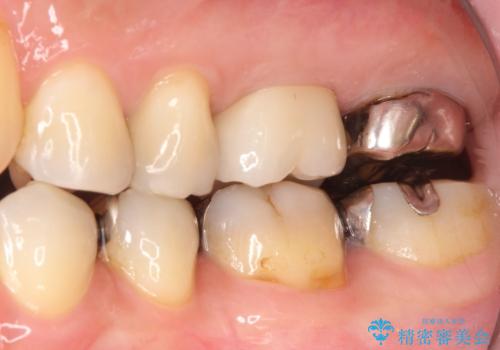

【再根管治療】オールセラミッククラウンによる修復

- 治療途中の歯があることを主訴に来院されました。

根管治療を行なったのちオールセラミックにて修復治療を行なっております。

第二大臼歯の治療は希望されませんでした。